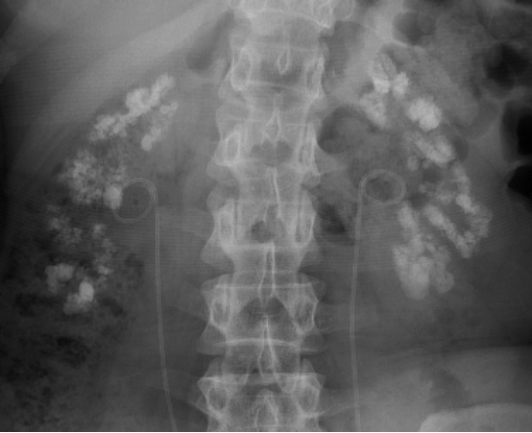

1.KUB(尿路平片):肾乳头和(或)锥体区可见簇状、扇形排列或放射状分布的多发高密度影。

图3 MSK结石的KUB,双侧肾区见多发密集的高密度影,结石呈簇状、放射状或粟粒状分布。